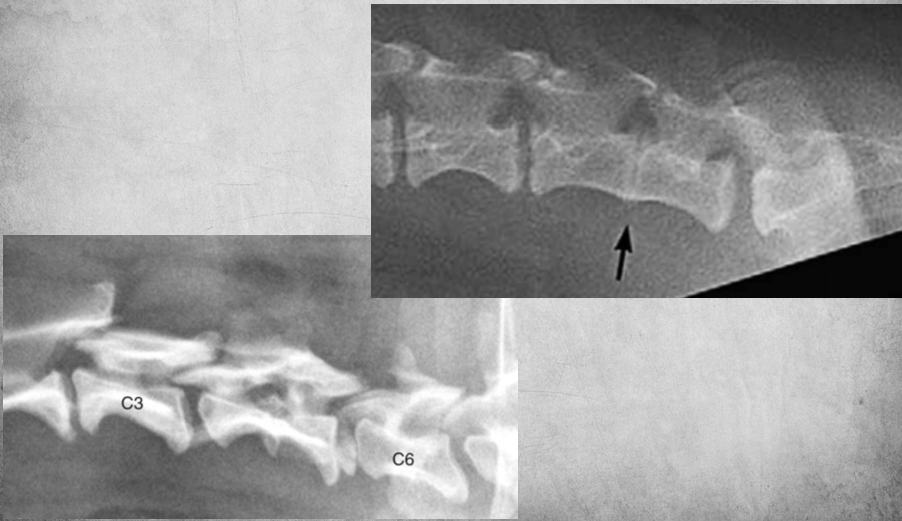

17

Q

identify anomaly

A

Hemivertebra

Failure of formation of a part of the vertebral body. The vertebra is missing bone part ventrally or dorsally.

Seen in Lateral view, Wedge shape.

More common in brachys but found in others as well. Can cause pain.

18

block vertebrae so fusion of two vertebra that should normally be separate vertebrae. (left image)

how to tell if its fusion or loss of intervertebral disc?

Check the margin, is there any time of delineation? (right image)